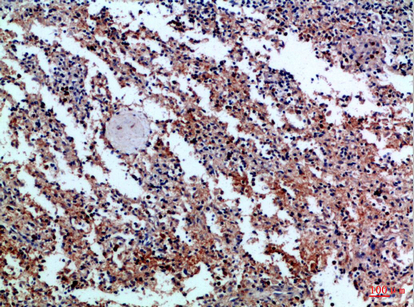

Product Image |

|

| IHC | 1/50-1/100 |